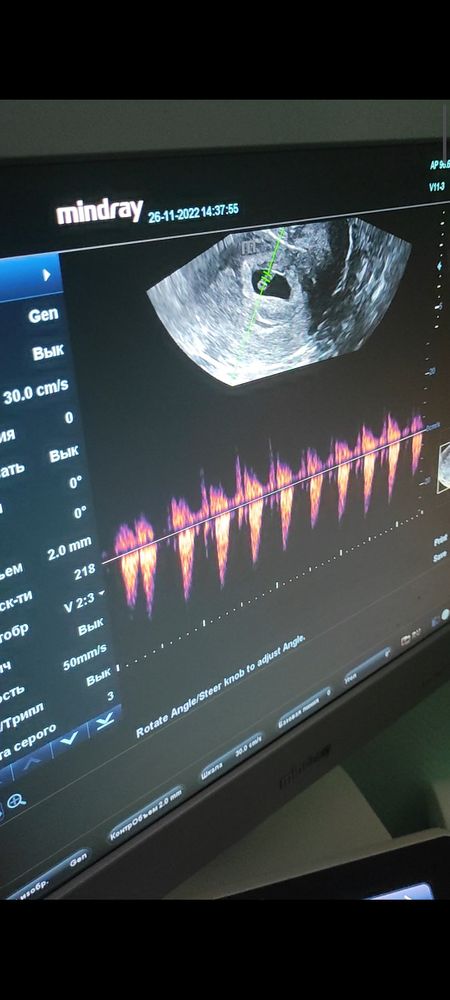

Узи на 31дпп😍

J Sha , да, обязательно)) это как раз скрин с видео, где со звуком

16,1 неделя😊😊😊 9дпп🤰Полёт нормальный🥰